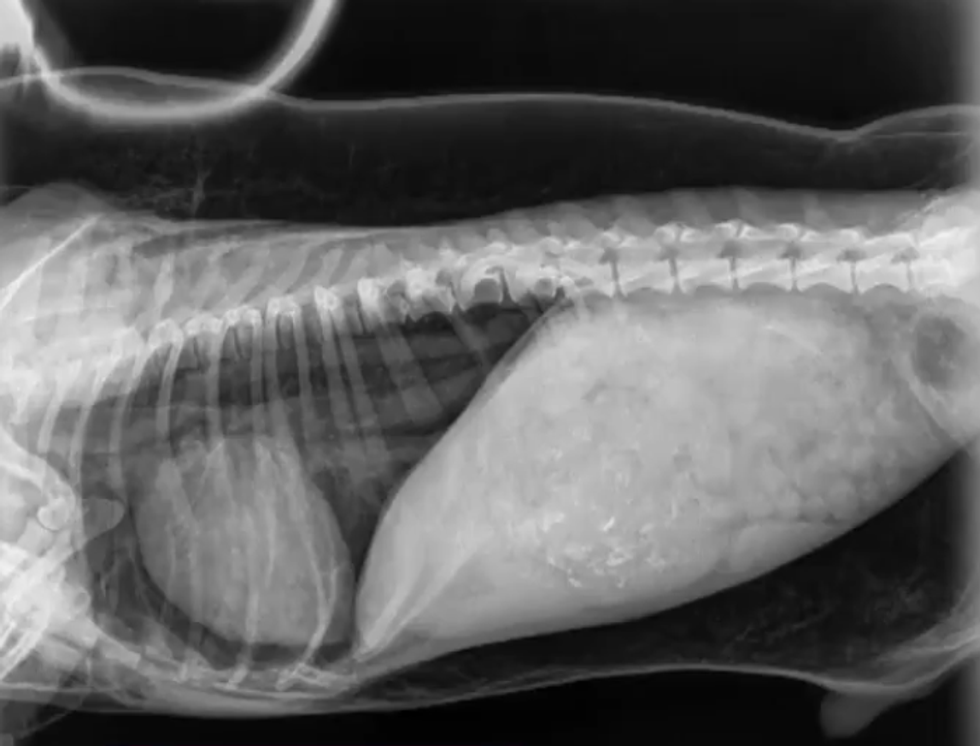

An injury left a hole in his windpipe, causing his face to inflate when the leaked air remained trapped underneath his skin and forced his heart to lift off the sternum.

Lab tests revealed that Trevor suffered from an abnormal condition called sub-cutaneous emphysema, in which air is trapped under a layer of skin.

While the cause in Trevor's case is unknown, the condition is a result of a puncture in respiratory or gastrointestinal systems usually caused by penetrating trauma such as gunshot or stab wounds, according to Wikipedia.

There were no external injuries that would explain how air had got under the skin, so we suspected that an internal injury to the airway could have been allowing the air in.

Every time he took a breath, some of the inhaled air escaped through a hole in his windpipe.